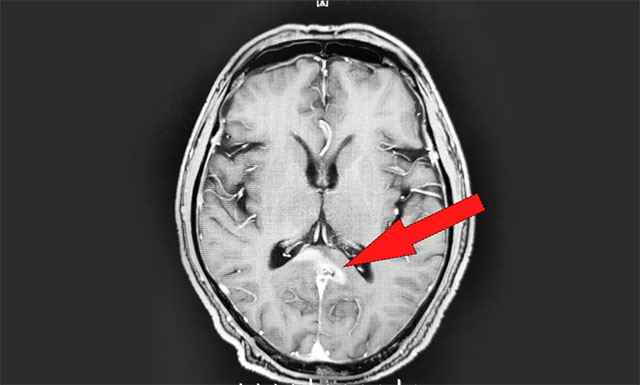

年过六旬的男性患者江某(化名),于2018年进行体检时被告知脾脏肿大,但由于当时并无不适症状,患者没有太在意。2019年11月中旬,患者突感身体不适,头晕胸闷恶心,就诊于当地医院。行头颅增强核磁检查后,诊断其为胼胝体压部及右侧丘脑淋巴瘤,当时暂未发现转移迹象。

▲ 放疗前 MRI 影像